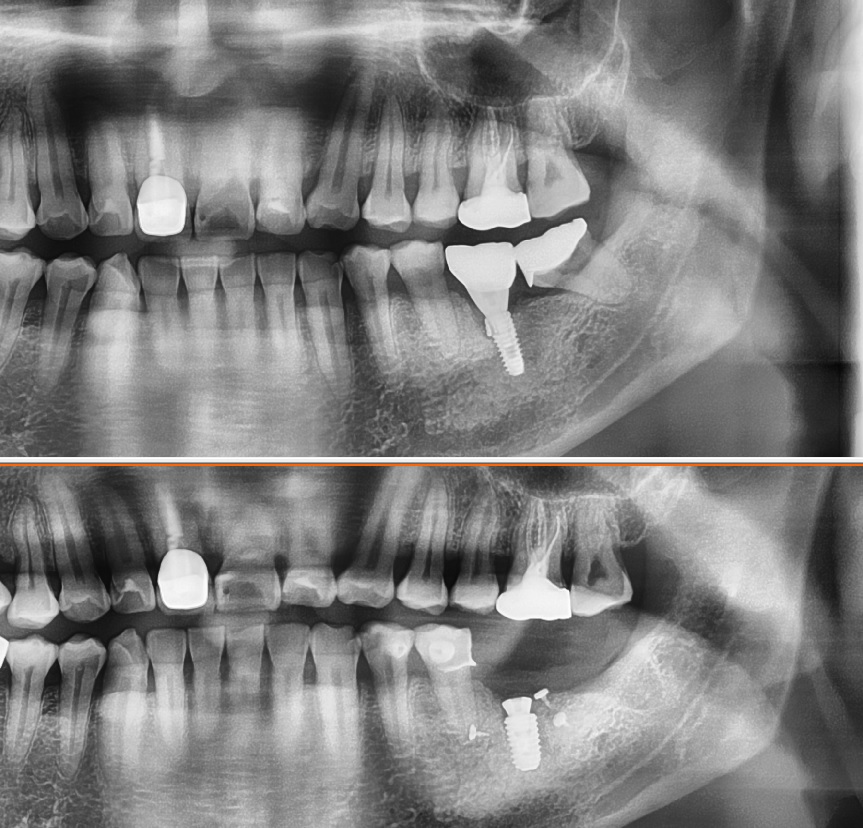

위에 케이스를 치료한 사진을 보도록 하겠습니다

먼저 부러진 임플란트의 제거

일단 부러진 임플란트의 경우

수리를 할 수 있는 방법은 없습니다

무조건 제거를 해야 하는데요

이 제거하는 것도 엄청난 일입니다

하나하나 일일히 깍아내서 제거를 하는데요

마지막으로 제거가 완료되면

안그래도 부족한 치조골이

더 부족하게 된 사진을 볼 수 있습니다

그렇다면 이렇게 부족한 치조골은

어떻게 해야할까요

부족한 부분에 그냥 다시 임플란트를 시술한다면

나중에 결국 다시 5년도 못쓰고 빼야하는 경우가 옵니다

아래 그림은 임플란트 제거후 3개월이 지난다음

재수술을 한 케이스 입니다

주변에 본택이라고 하는 부분이 보이는데요

이런 부분은 골이식을 하고 직경 5.0이상의 임플란트를 식립하였습니다

골이식 부분을 차폐막이라는 걸로 고정을 한 술식입니다

치조골 이식에서 상당히 많으 쓰이는 부분인데요

이렇게 치조골 이식이 많이 된 경우

6개월 이상 기다려야 하는 경우도 있습니다

임플란트 제거후 치조골 이식술과 직경5.0임플란트 재식립

임플란트 제거후 치조골 이식후 5.0 직경의 임플란트를 재수술 하였습니다

전후 사진을 보면 확실히 직경이 달라진걸 느낄 수 있습니다